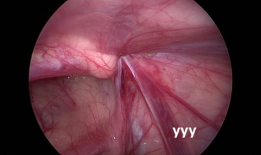

疝气手术视频,从术前准备到术后恢复

你有没有想过,当你在网上搜索“疝气手术视频”时,会出现什么样的画面呢?今天,就让我带你一起揭开这个神秘的面纱,看看那些让人既好奇...

2025-08-22 55 -